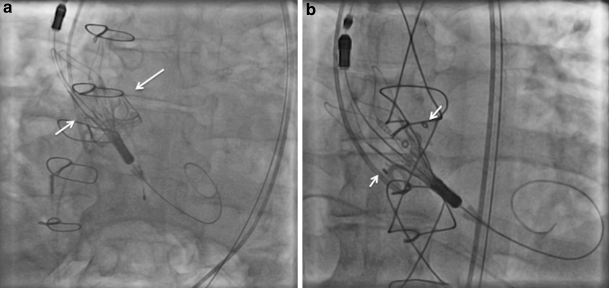

A 73-year-old man underwent transfemoral ViV-TAVI for severe stenosis in his 25-mm Carpentier-Edwards Perimount bioprosthesis. After balloon predilatation, a medium-size Accurate Neo was advanced to the bioprosthetic annulus. First, its upper part was released with the upper crowns positioned below the superior margin of the pre-existing bioprosthesis (Fig. 1a; [1]). Next, the device was deployed by releasing the lower crowns without ventricular pacing (Movie-1). The results were excellent.

A 79-year-old man underwent transfemoral ViV-TAVI for severe regurgitation of his 27-mm Mosaic bioprosthesis. A small-size Accurate Neo was deployed with its upper crowns positioned along the eyelets of the bioprosthesis (Fig. 1b). After balloon postdilatation, a paravalvular leak was reduced to trace.

Fig. 1

a Positioning of an Accurate Neo device inside a Carpentier-Edwards Perimount aortic bioprosthesis with its upper crowns sitting just below the superior margin of the bioprosthesis (arrows). b Positioning of an Accurate Neo device inside a Mosaic aortic bioprosthesis with its upper crowns positioned along with the eyelets of the bioprosthesis (arrows)